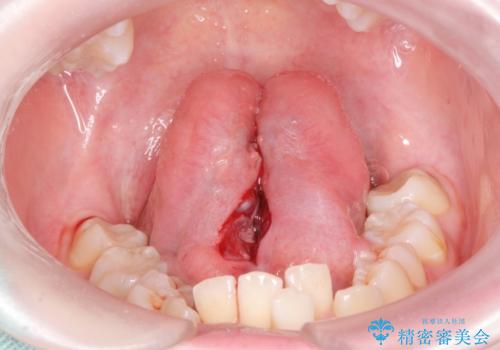

- 舌小帯を切除したいとの事で来院。

麻酔をして舌小帯切除術を行いました。